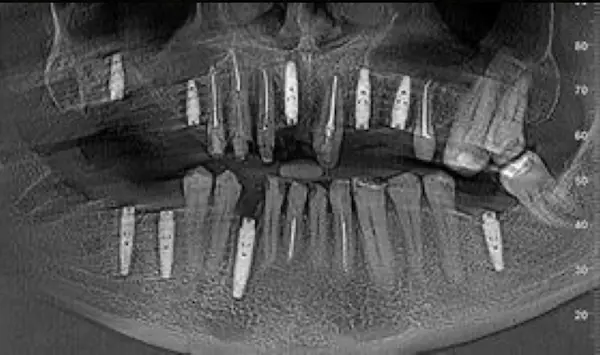

Сканы КТ имплантации зубов, 2026-04-18

Скан КТ, 2026-04-18

Сканы КТ имплантации зубов, 2026-04-18

Скан КТ имплантации зубов, 2026-04-17

Сканы КТ имплантации зубов, 2026-04-18

KT: имплантация зубов DentalKnysh, 2025-01-03, сканы

KT: имплантация зубов DentalKnysh, 2025-01-03, сканы

KT: имплантация зубов DentalKnysh, 2025-01-03, сканы

КТ имплантации зубов в DentalKnysh (10 имплантов), 2023-11-03

Имплантация зубов (13 шт) и 2 синуслифтинга 2023-10-06

С 2023-09-05 по 2023-09-09 сканы КТ от 6 до 12 имплантов в DentalKnysh (4 фото):

Синуслифтинг и имплантация зубов, 6 имплантов, all-on-6, КТ скан 1, 2023-08-31

Фото отчет Имплантация зубов, 6 имплантов, КТ скан 3, 2023-08-31

Фото отчет Имплантация зубов, 8 имплантов, all-on-4, КТ скан 1, 2023-08-31

Фото отчет 2 синус-лифтинга и 8 имплантов 2023-05-18